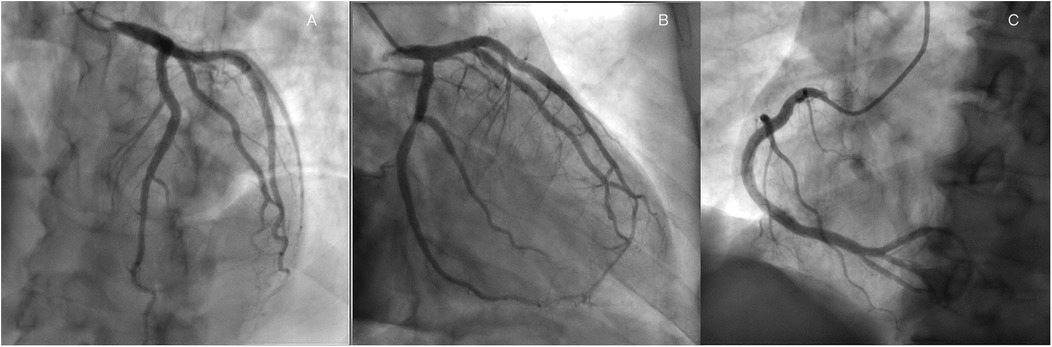

A 60-year-old man was found to have a liver-occupying lesion during a medical checkup. He underwent laparoscopic liver resection of segment 7 and was diagnosed with hepatocellular carcinoma (HCC) via liver biopsy in May 2022. Subsequently, he was initiated on a combination therapy involving tislelizumab (200 mg q3w) and lenvatinib (8 mg qd) from June 2022. Throughout the tislelizumab and lenvatinib combination therapy, no significant complications were observed. An MR scan of the upper abdomen conducted three months earlier showed a rounded signal in the S6 segment of the liver, along with adjacent multiple abnormal signal nodules. On May 4, 2023, the patient was admitted to the hepatobiliary surgery department. No chest discomfort was reported, and his troponin level was negative. His temperature was 36.4°C, pulse rate 81 bpm, respiratory rate 20 breaths per min, and blood pressure 124/79 mmHg. Cardiac and pulmonary examinations revealed normal heart sounds without murmurs, as well as clear lung sounds. Abdominal examination indicated a soft and nontender abdomen without rebound tenderness. A treatment plan was established for anti-tumor therapy, involving toripalimab and lenvatinib/oxaliplatin/gemcitabine. However, shortly after the infusion of toripalimab, the patient experienced sudden chest pain, diaphoresis, and then syncope. Upon physical examination, his heart rate dropped to 50 beats per min, respiratory rate remained at 20 breaths per minute, and blood pressure decreased to 85/60 mmHg. Auscultation indicated normal heart sounds and no murmurs. The patient's face appeared pale, with no rash. The electrocardiogram (ECG) displayed ST-segment elevation of 0.1–1.0 mV in dynamic leads I, II, III, aVF, and V5–V6 (Figure 1A). Toripalimab was promptly discontinued, leading to the spontaneous resolution of symptoms after 10 min and a return of the ECG to baseline. Cardiac troponin I enzyme levels peaked at 0.080 ng/ml (0–0.034) around 18 h after symptom onset. The patient did not agree to undergo coronary angiography (CAG) due to the symptom relief. Coronary computed tomographic angiography revealed nonobstructive coronary arteries with mild stenosis, 11% stenosis in the left main artery (LM), 11% stenosis in the proximal-left anterior descending artery (pLAD), myocardial bridge-mural coronary artery in the proximal-left anterior descending artery and the distal-left anterior descending artery (dLAD), without stenosis in the left circumflex artery (LCX), 10% stenosis in the middle right coronary artery (mRCA), and 10% stenosis in the distal right coronary artery (dRCA). A transthoracic echocardiogram confirmed normal left ventricular size and function. Lipid-regulating drugs atorvastatin (20 mg/day) was prescribed, and the patient remained symptom-free in the subsequent days. Thus, he was planned to continue to implement a anti-tumor therapy course. However, on May 25, 2023, during toripalimab infusion, the patient experienced a recurrence of chest pain, diaphoresis, and dizziness. Physical examination indicated a heart rate of 68 bpm, respiratory rate of 26 breaths per min, and blood pressure of 63/40 mmHg. Auscultation indicated normal heart sounds and no murmurs. The ECG revealed dynamic ST-segment elevation of 0.1–0.2 mV in leads II, III, aVF, and V5–V6 (Figure 1B). Toripalimab was immediately discontinued, leading to symptom resolution within 30 min, and the ECG returned to baseline (Figure 1C). Cardiac troponin I enzyme levels were measured at 0.138 ng/ml. A transthoracic echocardiogram revealed an ejection fraction of 60%, with normal left ventricle's size and no significant regional wall motion abnormalities. Following the doctor's advice, he had CAG examination. Subsequent CAG confirmed patent coronaries, without any substantial flow-limiting lesions (Figure 2). The patient did not agree to undergo coronary vasospasm provocation testing due to possible serious adverse event risk, and refused further examination to further confirm the cause. However, based on the patient's symptoms, ECG findings, and coronary angiography, a diagnosis of CAS was established. The patient was prescribed diltiazem sustained-release capsules (30 mg, four times daily) and atorvastatin (20 mg/day).

Figure 2. Coronary angiography revealed nonobstructive coronary arteries in the LAD, (A), LCX, (B) RCA (C).